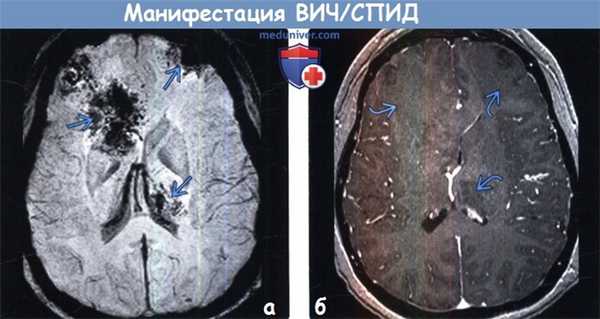

Диагностика связанных с ВИЧ/СПИД инфекций, опухолей головного мозга по КТ, МРТ

1. Общие характеристики манифестации ВИЧ/СПИД:

о Первичная лимфома ЦНС (ПЛЦНС): накапливающие контраст очаги поражения, часто имеющие геморрагический/некроти-ческий характер и локализующиеся в структуре базальных ганглиев, перивентрикулярного БВ

(а) КТ с контрастированием, аксиальный срез: у ВИЧ-положительного пациента с припухлостью кожи волосистой части головы определяется объемное образование мягких тканей с инфильтративным типом роста, вызывающее утолщение кожи волосистой части головы левой лобной области. При биопсии была обнаружена саркома Капоши. Саркома Капоши относится к группе СПИД-определяющих опухолей (СОО).

(б) МРТ, ДВИ, аксиальный срез: у ВИЧ-положительного пациента, поступившего в медицинское учреждение с изменениями чувствительности и судорожным синдромом в лобных долях и таламусе слева определяются крупные зоны ограничения диффузии.